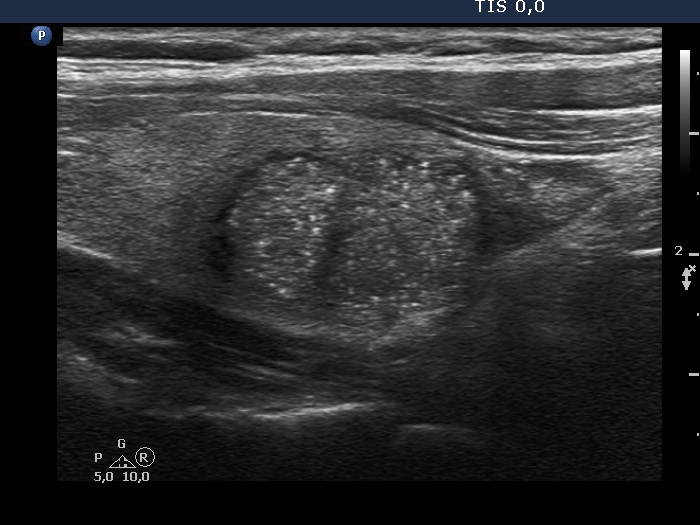

Ultrasonography. The thyroid was echonormal. There was a hypoechogenic nodule in the right lobe. The nodule had numerous punctate echogenic granules.

The echogenic figures are very difficult not to interpret as microcalcifications. Nevertheless, thorough analysis reveals that some of the bright granules has a short tale, and great proportion of these figures are related to ventral tiny hypoechoic areas, probably cysts. Moreover, there are not only echogenic granules but also short echogenic lines within the nodule. Taking all in all, these echogenic figures are very suspicious being microcalcifications.

The ACR TIRADS is the only one which does not use the term 'microcalcification', instead they use the term 'punctate echogenic foci', which includes microcalcifications and short-tail comet-tail artifact. This example stands for the advantage of the ACR terminology.